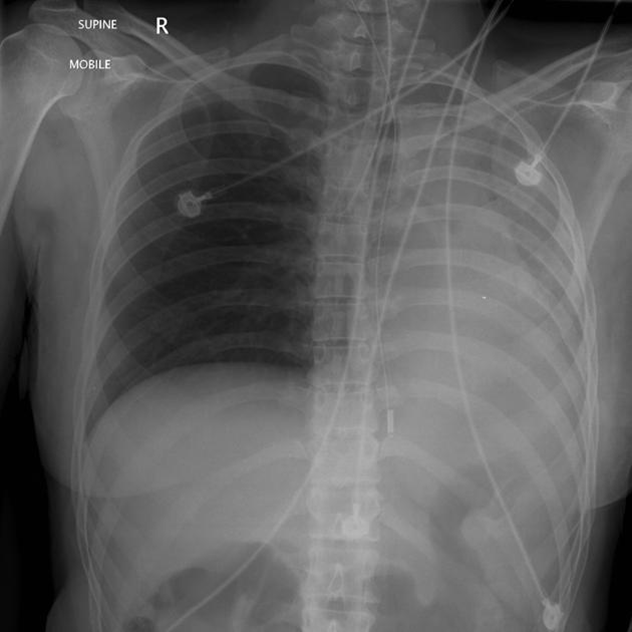

This could happen if the ET tube is advanced too far.

What is a right mainstem intubation?

This could occur if a mainstem intubation is not realized for a while.

What is an atelectatic L Lung?